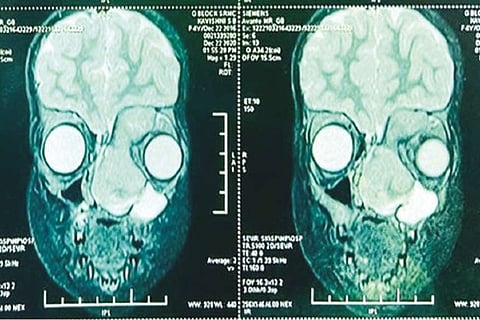

Despite treatment, the tumour had grown and blocked both nasal passages. It had also extended into the poor girl’s left eye and was displacing it “outwards and downwards.” Further Investigations by expert doctors at SRM revealed a very extensive tumour in the left nasal cavity with extension into the left eye, engulfing the left eyeball and displacing the eye outwards.

The team of doctors, including Prof Lt Col Dr A Ravikumar, Dr Shivapriya, Dr B Gayathri, Dr Radhakrishnan, Departments of ENT, Anaesthesiology and Ophthalmology, SRM Medical College Hospital and Research Centre, first did a very fine procedure on the girl child recently so that the tumour was “debulked” using a nasal endoscope and only a small incision externally. This first procedure was necessary as the tumour had become hard in the wake of the chemotherapy and had made dissection difficult.